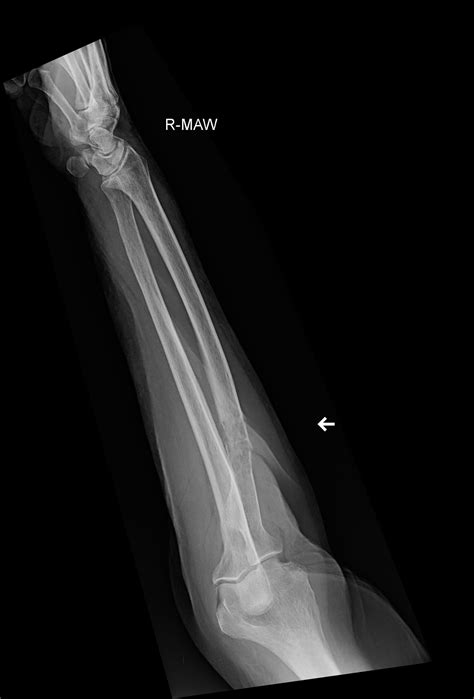

Position Purpose

Anteroposterior (AP) View The arm is flat on the table, palm facing up, providing a front-to-back view of the radius and ulna.

Lateral View The arm is turned 90 degrees, showing the side profile of the bones to check for displacement or angling.

Once the forearm X-ray images are captured, they are sent to a radiologist—a doctor who specializes in interpreting diagnostic images. They will look for:

• Fractures: Whether the bone is broken completely, partially (a hairline fracture), or fragmented (comminuted fracture).

• Alignment: Checking if the broken ends of the bone are touching or if they have shifted.

• Dislocations: Ensuring the bones of the elbow and wrist remain properly seated in their joints.

• Pathology: In rare cases, the X-ray can reveal bone tumors, infections, or signs of bone diseases that may have weakened the structure.